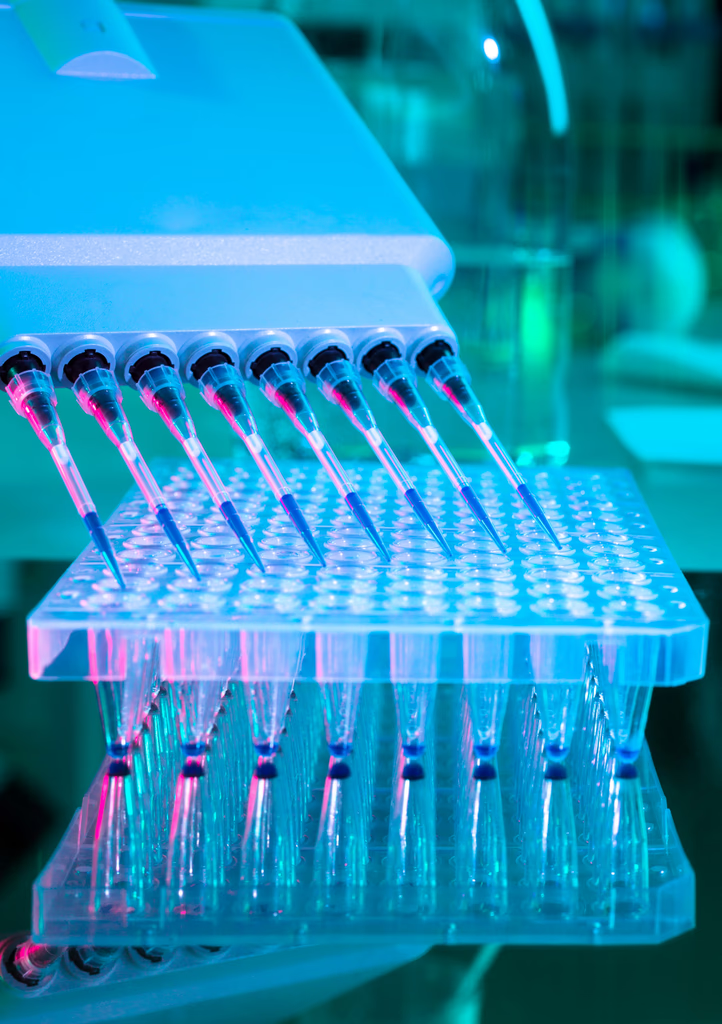

Pharma requires reproducible, high-throughput human tissue assays that integrate with existing R&D workflows and regulatory needs.

Scalable drug testing to predict efficacy and toxicity with greater human relevance.

High-throughput tissue plates enable rapid, reproducible assays that plug into existing R&D pipelines, shortening timelines, lowering per-assay cost, and accelerating go/no-go decisions.